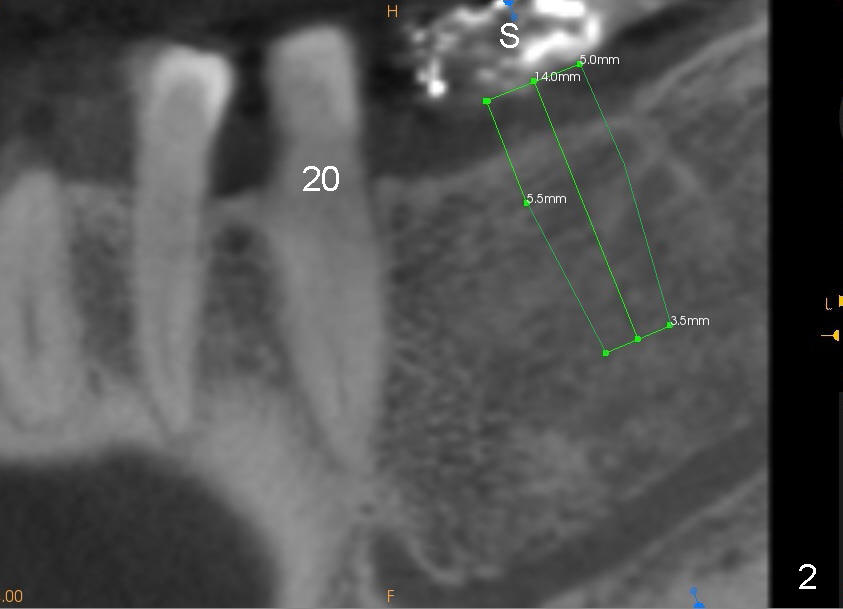

A 45-year-old man is a smoker (half pack a day). He returns for perio maintenance every 3 months. The teeth #18 and 19 have been extracted for long with supraeruption of #14 and 15 (Fig.1 arrows). CT confirms sufficient bone height (Fig.2) and width (Fig.3). Bone density is type II, as shown by CT and drilling. Relatively short implants are placed as deep as possible considering supraeruption of the opposing teeth (Fig.4 (4.5x14 and 5x14 mm taps at sites of #19 and 18, respectively) and Fig.5 (5x14 mm and 6x14 mm gingiva-level implants (I)). In order to avoid damaging the submandibular fossa, the implant at the site of #18 is tilted lingually (Fig.6). When short abutments (3 mm in height) are placed, there is enough clearance to place perio dressing. The abutment at the site of #18 becomes prematurely loose. It has to be removed 4 days postop. There is no sign of infection. Perio dressing is removed by the patient 7 days postop. He returns to clinic 8 days postop (Fig.7) for the remaining abutment to be removed. The wound appears to be healing normally.